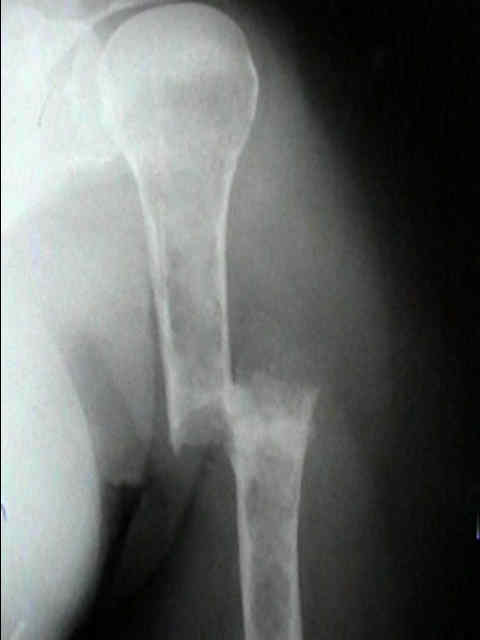

Hallazgo radiológico característico

- Enfermedad ósea lítica: activación osteoclástica e inhibición osteoblástica → lesiones “en sacabocado”, fracturas y dolor.

| B Lesiones óseas líticas / fracturas por compresión atribuibles | ≥1 lesión lítica (CT/PET-CT/WB-LDCT; típicamente ≥5 mm) | |

- Dolor óseo (columna, costillas, pelvis), fracturas por fragilidad, pérdida de altura vertebral.

- Radiología/TC: lesiones osteolíticas “en sacabocado”, osteopenia difusa, fracturas vertebrales.